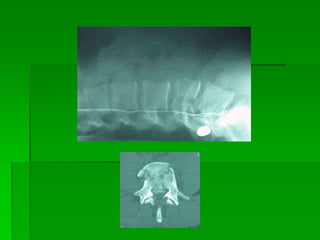

FRATURA COMPRESSÃO TORÁCICA

BAIXA

As lesões ocorrempor: -Flexão, extensão, rotação, compressão por impacto axial ou combinação desses mecanismos. -Achatamento -Fratura cominutiva -Fratura luxação – articulação intervertebral e pedículos Mecanismo de Trauma Raqui-Medular com fratura

• 24.